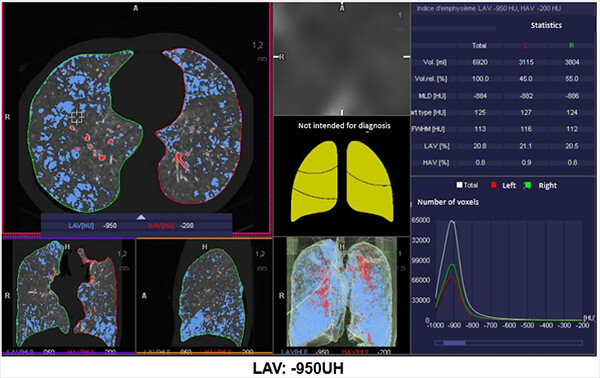

Damaged Alveoli

This image shows us an example of images where the damaged alveoli are highlighted in blue.